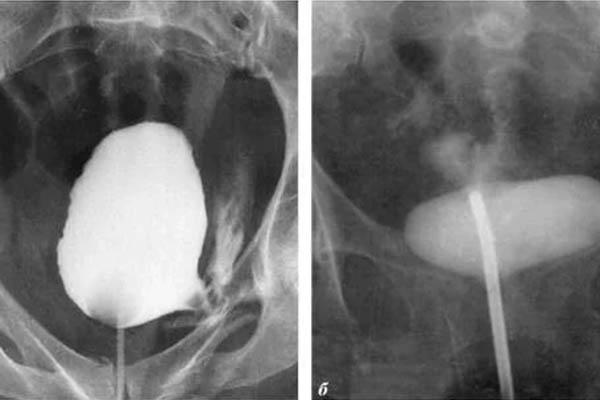

Saya ingin menunjukkan beberapa foto tentang apa yang terjadi pada sistem genitourinari dan organ dalam lainnya dari seorang pria ketika dia berhenti berhubungan seks.

alt_text

Seperti inilah peradangan prostat karena stagnasi di dalamnya (dengan tidak adanya pengosongan testis, yang terjadi saat berhubungan seks). Peradangan yang berkepanjangan pertama-tama mengarah ke adenoma, dan kemudian ke kanker prostat (dari mana, menurut statistik, 38% pria meninggal). Dengan tidak adanya seks, ini selalu terjadi, itulah sebabnya adenoma dianggap sebagai penyakit orang tua.